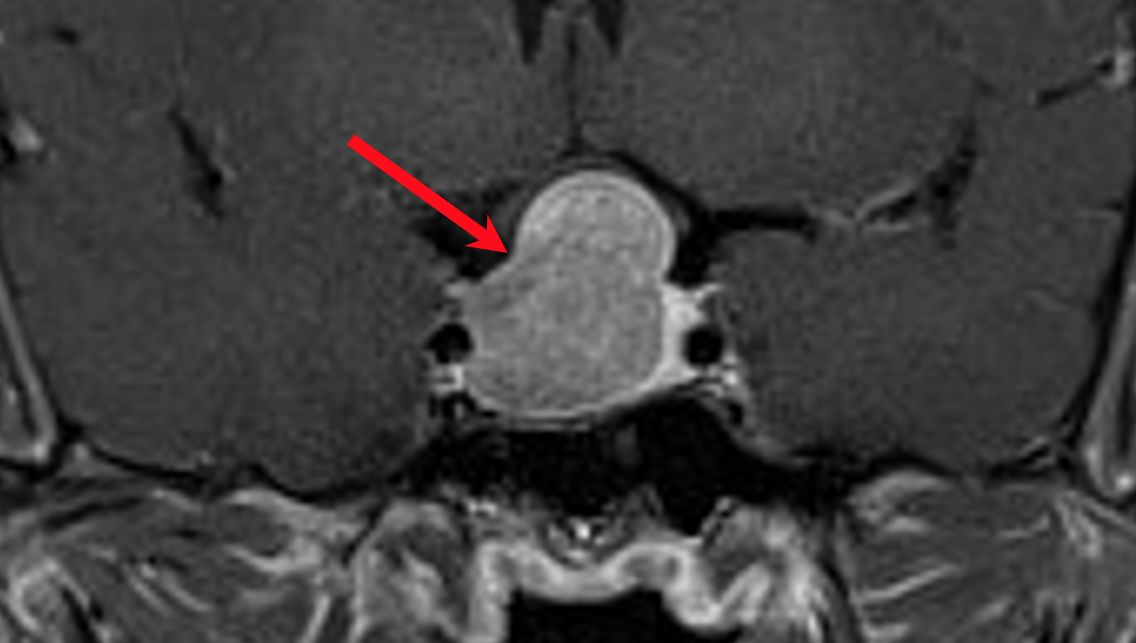

這名個案陳先生經由內分泌暨新陳代謝科診斷為肢端肥大症後,核磁共振影像進一步定位長在腦下垂體的腫瘤。院方透過腦瘤微創手術將腫瘤連根拔起,陳先生的大手大腳變化才逐漸改善,目前仍持續在門診追蹤。